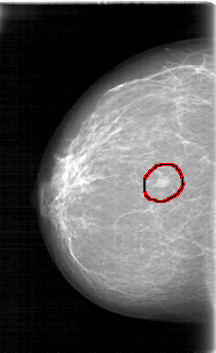

D_4090_1.RIGHT_MLO

RIGHT_MLO LINES 5236 PIXELS_PER_LINE 3316 BITS_PER_PIXEL 12 RESOLUTION 43.5 OVERLAY

FILE: D_4090_1.RIGHT_MLO.OVERLAY

TOTAL_ABNORMALITIES 1

ABNORMALITY 1

LESION_TYPE MASS SHAPE OVAL MARGINS ILL_DEFINED

ASSESSMENT 0

SUBTLETY 5

PATHOLOGY BENIGN

TOTAL_OUTLINES 1

BOUNDARY